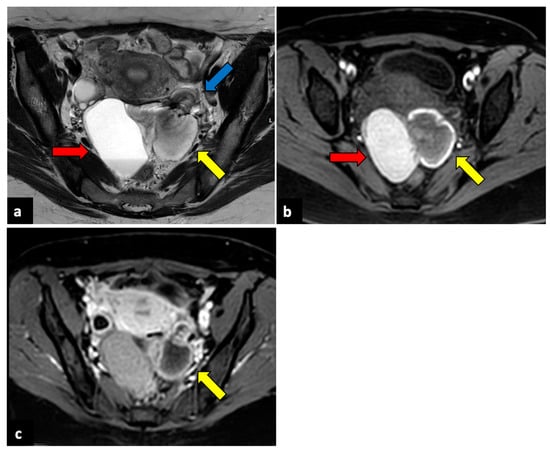

Acute bleeding or rupture of functional (follicles and corpus luteum) ovarian cysts is one of the most common causes of APP in young women [30]. In severe cases, it can be associated with haemorrhagic shock and hypotension and, thus, can be potentially life-threatening. Clinically, it may overlap with an ectopic pregnancy, which should be ruled out by evaluating serum human chorionic gonadotropin (hCG) levels. In the case of acute haemorrhage, upon a US evaluation, the cyst is isoechoic in comparison with the ovarian stroma. It can mimic an enlarged ovary, while a thick irregular wall of increased peripheral vascularity (“ring of fire”) may be seen during a colour Doppler US [31]. In case of cyst rupture, chronic bleeding, septations, and liquid-sediment levels can be detected. At the CT evaluation, haemorrhagic cysts are typically heterogenous lesions with hyperdense areas. If a haemorrhagic cyst ruptures, hyperdense ascites is generally seen in the pouch of Douglas and sometimes in the upper abdomen (Figure 4) [16,32]. During MRI, haemorrhagic cystic lesions typically show a high signal on T1-weighted images and an intermediate-to-low signal on T2-weighted ones. In the case of haemorrhagic cyst ruptures, haemoperitoneum can be seen as free peritoneal fluid characterised by areas of both low and high signal intensity depending on the extent of blood-clot formation [5].

Figure 4.

Ruptured ovarian corpus luteal cyst. CT axial (a), sagittal (b), and coronal (c) scans of a twenty-eight-year-old woman with acute right-sided pelvic pain. HCG test was negative. Images show a hypodense cystic lesion in the right adnexa, with thick and enhancing walls (yellow arrows). A focal discontinuity in the posterior wall is observed. Free pelvic fluid is also visible. The patient was treated conservatively.